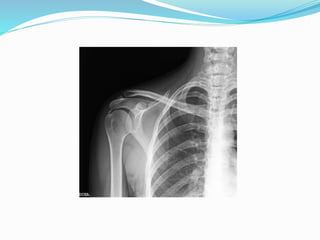

El documento trata sobre la anatomía y la funcionalidad del complejo articular del hombro, enfocándose en espacios quirúrgicos específicos en la región posterior. Se presenta información relevante sobre la cintura escapular y su relación con el hombro. El análisis realizado por el Dr. Luis Francisco Chávez Flor abarca aspectos clave para la comprensión de procedimientos quirúrgicos en esta área.